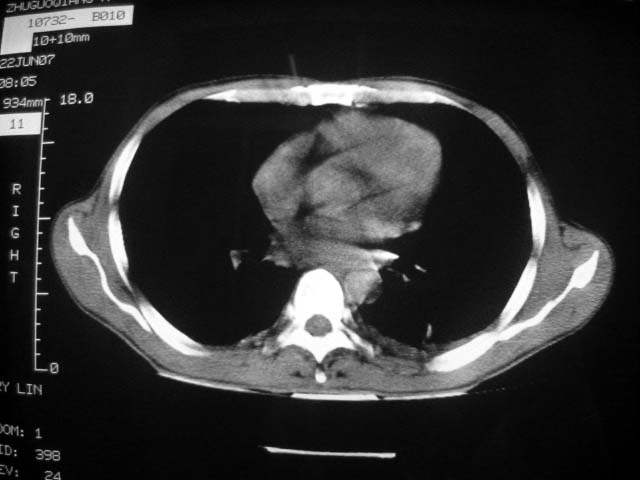

标题: CT7988D:近期图像 出乎意料!

从ct7988c 至今未用任何抗生素及抗痨药,维持保肝治疗。患者低热、咳血渐消失。

07年6月22号复查

前几次大家认为是转移癌,但此次复查病灶却明显吸收好转,不支持诊断。请大家讨论。[emb10]

患者现无咳嗽咳痰及咳血,肝功好转,血清白蛋白降低,球蛋白升高,白球比小于0.5.少量腹水。

根据前后片比较应该考虑迁徙性肺脓肿,回帖相差甚远是因为前后片变化太大出乎大家意料之外,这就是影象诊断要结合临床复查对比的必要性,

回顾既往片,病变明显吸收,缩小,未经治疗,不支持肺转移瘤,可能为肺结节病或韦格氏肉芽肿

支持韦格氏肉芽肿

患者近期复查胸ct正常,轻度肝功异常,保肝、抗病毒(拉美夫叮)治疗中。